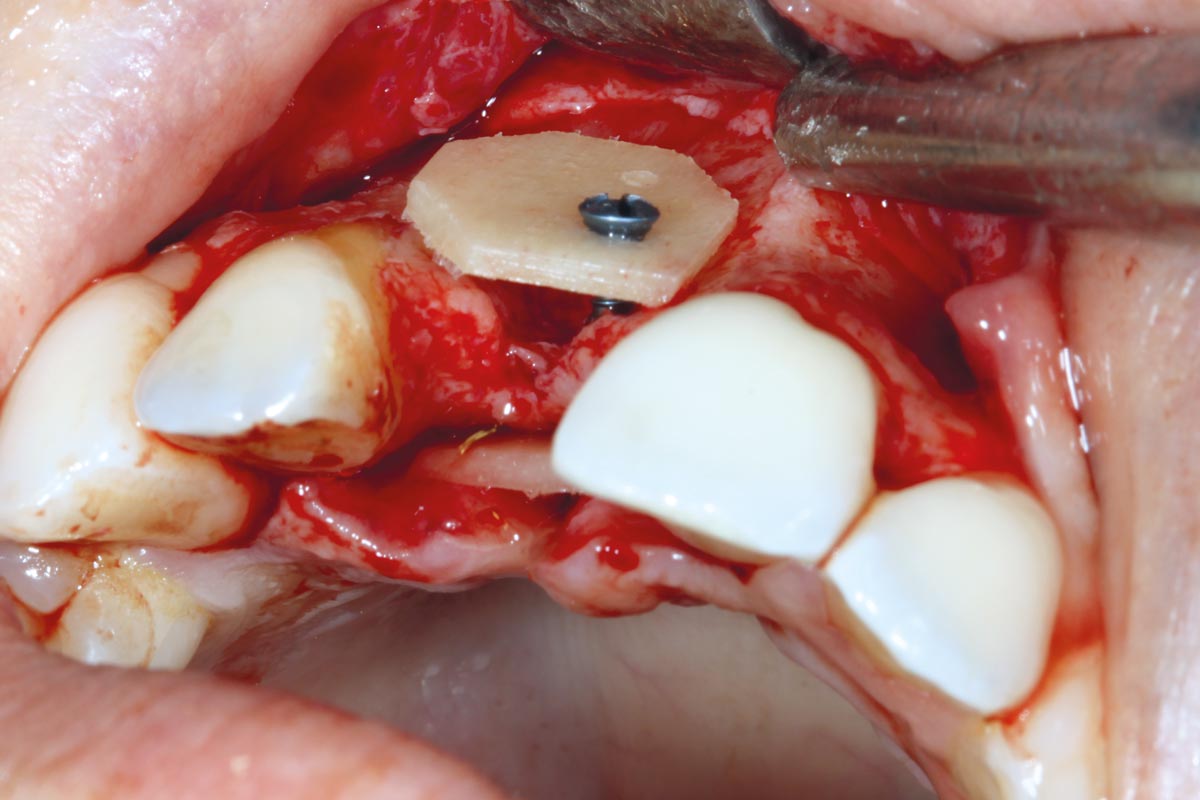

maxgraft® cortico at combined defect palatally and facially - Dr. K. Höckl